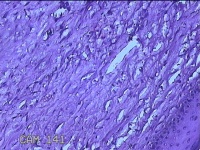

右膝部皮肤肉芽肿

性别

男

年龄

13岁

临床诊断

皮肤肉芽肿

一般病史

外伤后,出现右膝部皮肤肉芽肿形成。

标本名称

大体所见

灰白暗红色带皮肤样组织2.8x1.8x1.3cm,表面糜烂,切面灰白粉红色,质软。

图2